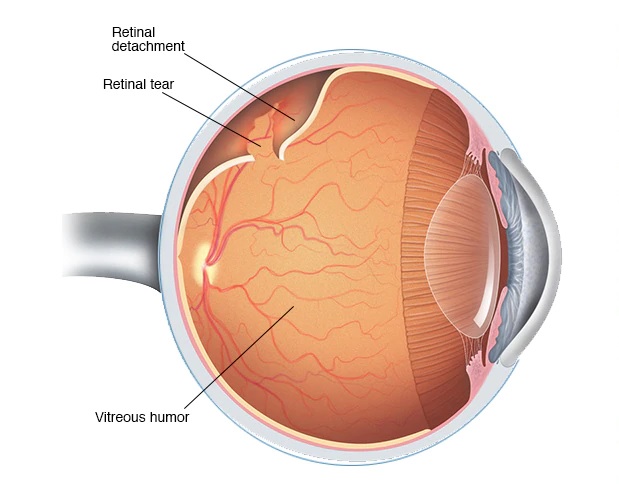

Detachment is the separation of rods and cones, we call them neuroepithelium, from the underlying pigment epithelium by the accumulation of fluid between them. This disrupts the power of the outer layers of the retina, which leads to rapid loss of vision.

分离是棒和视锥的分离,我们称它们为神经上皮,是通过它们之间的积聚而从下面的色素上皮中分离出来的。 这会破坏视网膜外层的力量,从而导致视力Swift丧失。

Retinal detachment in its type may be dystrophic (rhematogenous), traumatic and secondary. The secondary is not considered as an independent clinical form, but is only a complication of the underlying eye disease — inflammation, tumor, vascular or congenital diseases.

视网膜脱离的类型可能是营养不良(生发性),外伤性和继发性的。 继发性疾病不被认为是独立的临床形式,而仅仅是潜在的眼部疾病(炎症,肿瘤,血管或先天性疾病)的并发症。

The reason for regmatogenous (regma — rupture) retinal detachment, or, they say, primary detachment, as is already clear, is a rupture or rupture of the retina. As a rule, the gap occurs somewhere on the periphery, close to the equator of the eye, in the area of thinning and dystrophy.

他们已经说过,视网膜变性或视网膜原发脱离的原因是视网膜形成或破裂。 通常,缝隙发生在变薄和营养不良的区域中,靠近眼睛的赤道的某个地方。

Comparing the eye with a camera in which there is a film, we can say that somewhere on the edge of the frame there appeared a scratch of the emulsion layer. Well, what of this, you say, because almost the entire frame and the most important thing — the center of the “composition” — is still visible well. It turns out that this is not true. Through the gap begins to penetrate the fluid, flowing under the retina and thereby peeling it from the underlying choroid. On film, it looks as if an emulsion layer starts to blister around the scratch and peel off from the substrate. A person at this moment sees a rather characteristic picture of a “gray curtain” at the edge of the visual field. Depending on the location of the gap, the “curtain” can either spread quickly (within several tens of hours), closing the entire field of view, or crawl more smoothly (for weeks)

将眼睛与装有胶卷的相机进行比较,可以说在镜框边缘的某个地方出现了乳剂层的划痕。 好吧,这就是您所说的,因为几乎整个框架和最重要的部分(“构图”的中心)仍然清晰可见。 事实证明这是不正确的。 穿过缝隙开始渗透流体,在视网膜下方流动,从而将其从下面的脉络膜剥离。 在胶片上,似乎乳液层开始在划痕周围起泡并从基材上剥离。 此时,一个人在视野的边缘看到了相当有特色的“灰色窗帘”图片。 取决于间隙的位置,“窗帘”可以快速传播(在几十小时内),关闭整个视场,或者可以更平滑地爬行(持续数周)

It is clear that if the gap is located in the upper parts of the eye, the fluid quickly goes down and the exfoliation passes rapidly. If the gap is located below, then the detachment slowly «crawls» up, and the progression will be slower. However, the adhesions between the retinal zones and scars will be more pronounced — the time for their formation will be more.

显然,如果间隙位于眼睛的上部,则液体会Swift下降,并且剥落会Swift通过。 如果间隙位于下方,则分离会缓慢地“爬行”,并且进展会变慢。 但是,视网膜区域和疤痕之间的粘连会更加明显-形成它们的时间会更长。